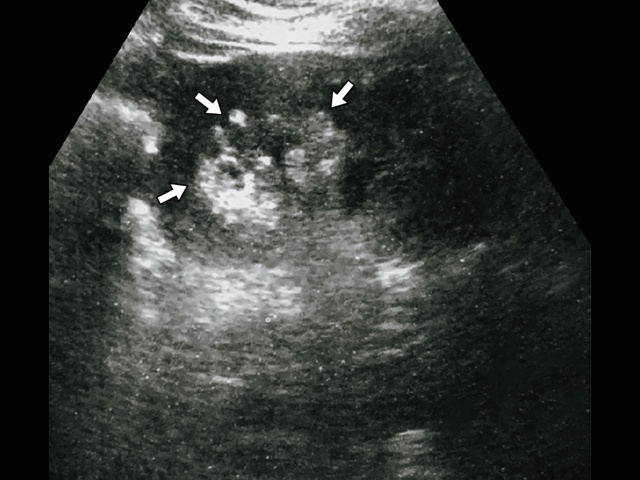

В качестве иллюстрации приводим результаты обследования пациентки Д., 47 лет. При диспансерном осмотре при УЗИ выявлены множественные гиперэхогенные образования от 3 до 7 мм, по типу АМЛ (рис. 7)

В обеих почках множественные гиперэхогенные образования различного диаметра с четкими контурами, без эффекта усиления.

Проведенная МСКТ полностью подтвердила полученные данные (рис. 8).

В обеих почках в корковом веществе определяются многочисленные образования с ровным контуром, размерами от 3 до 7 мм в диаметре, жировой плотности – 80 HU.